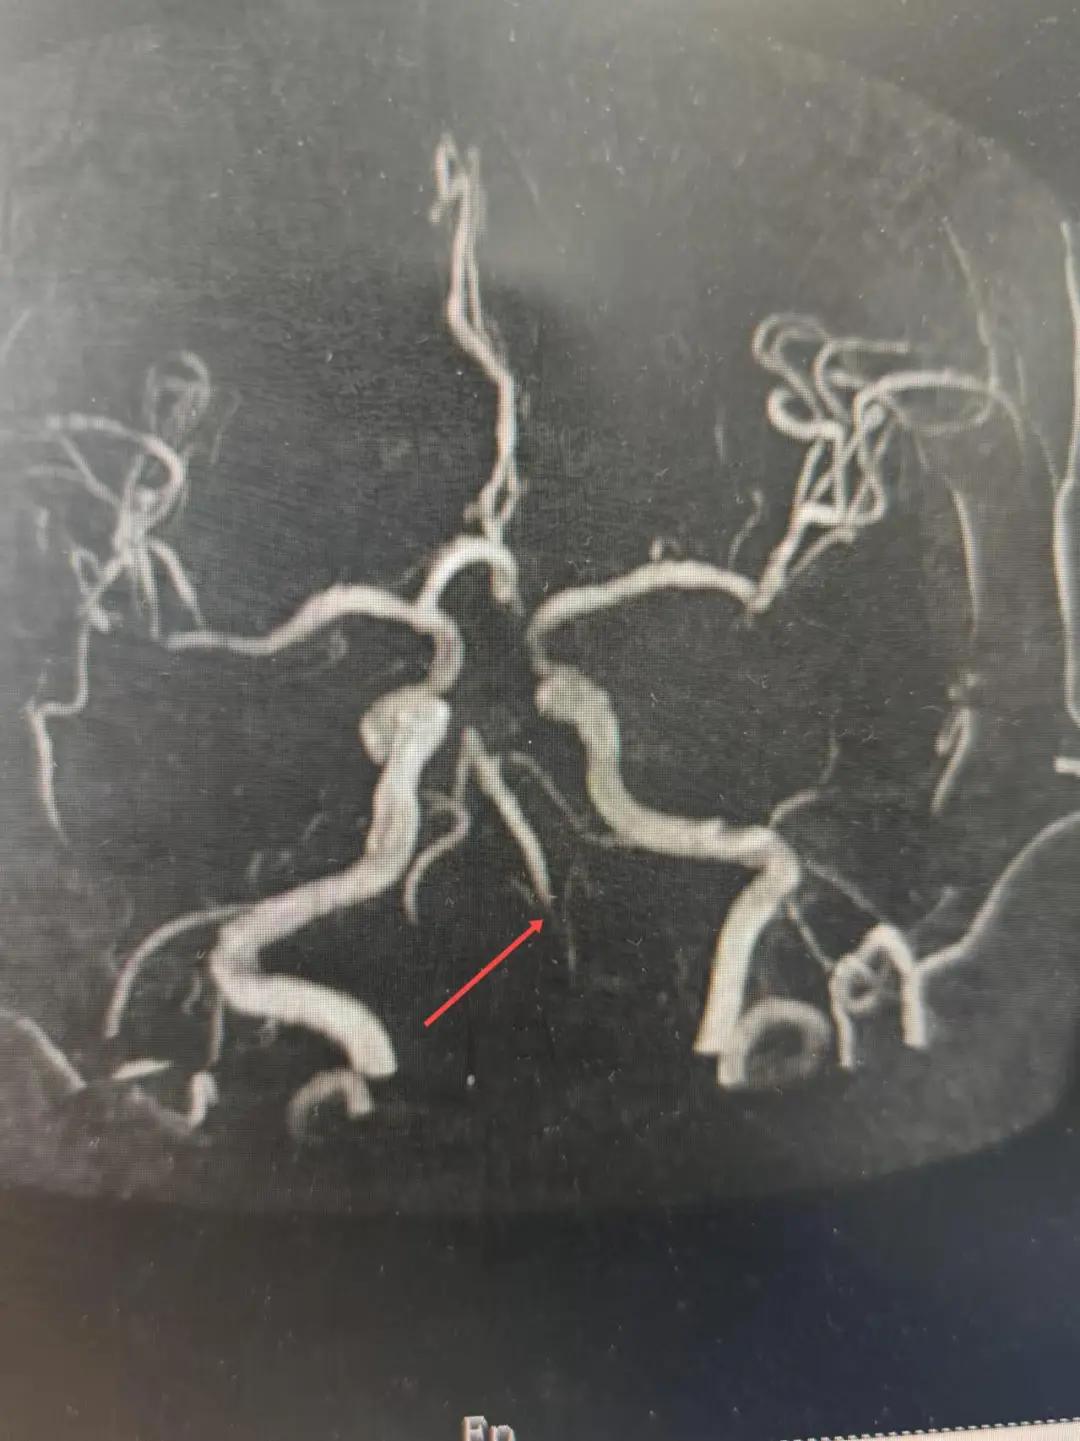

2024年12月19日,漯河市中醫(yī)院腦一科收治了一位79歲的女性患者?;颊咴谌朐呵?小時出現(xiàn)言語不利,右側(cè)肢體無力。腦一科醫(yī)師關(guān)卓杰接診后,全面評估患者病情,給予其靜脈溶栓,并急查頭顱MR。影像可見腦干、雙側(cè)枕葉、左側(cè)海馬旁回及丘腦新發(fā)梗塞灶,基底動脈閉塞。患者在靜脈溶栓完畢后仍出現(xiàn)陣發(fā)性言語不利、右側(cè)肢體無力、頭暈。立即進行科室間會診,副主任醫(yī)師彭壯考慮患者出現(xiàn)上述癥狀與其基底動脈閉塞后顱內(nèi)動脈代償不良有較大關(guān)系,且基底動脈閉塞有較高的致死率與致殘率,建議行急診取栓,降低患者死亡及殘障風險。家屬了解病情,知情同意后要求行介入治療。

磁共振MRA提示基底動脈閉塞